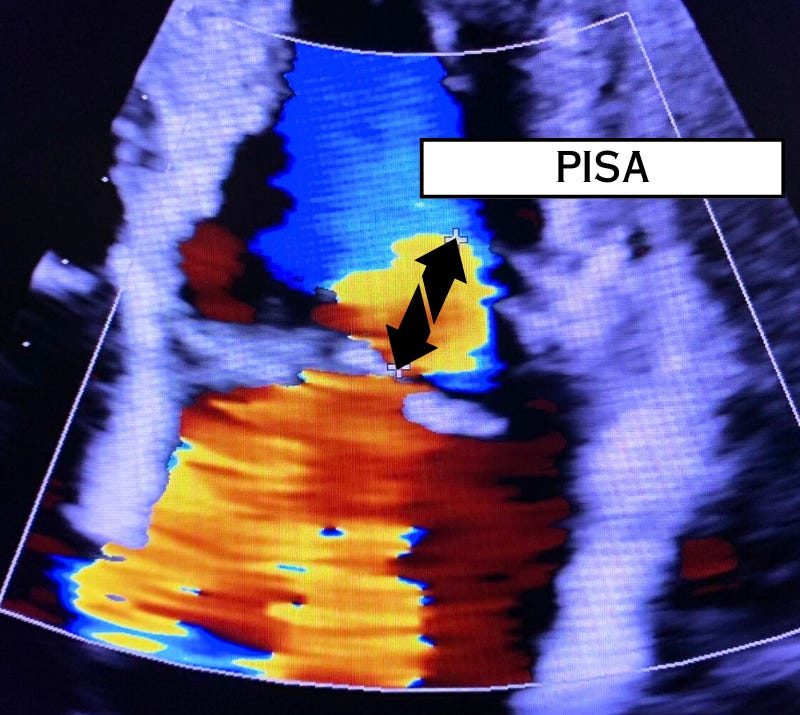

Who is PISA?

Quantifying the Degree of Mitral Regurgitation

The effective regurgitant orifice area (EROA) is calculated by using color flow Doppler and continuous wave Doppler. The proximal flow convergence of the jet (see below) combined with the maximum velocity will yield this area in cm2. This is referred to as proximal isovelocity surface area (PISA).

This quantification method requires a color baseline shif…